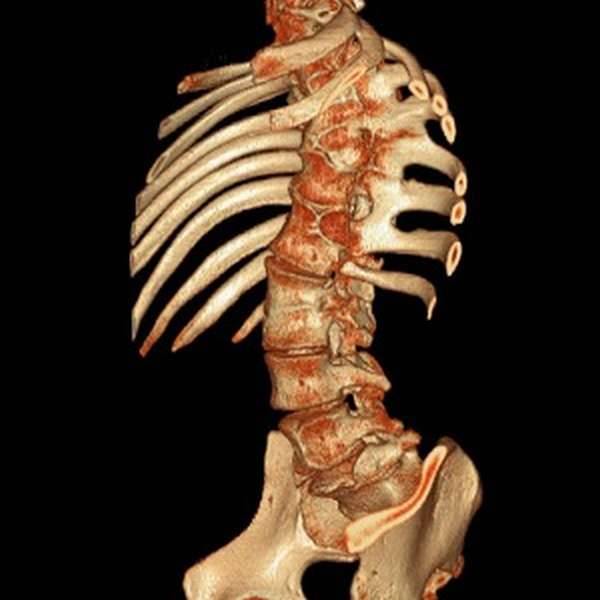

Границы отделов позвоночника не стабильны: пограничный позвонок одного отдела может принимать морфологические черты соседнего, уподобляться ему (ассимилироваться). Ассимиляции наблюдаются во всех переходных границах отделов позвоночника. Большое практическое значение имеют ассимиляции в пояснично-крестцовой границе — сакрализации и люмбализации. Обе эти аномалии развития удобнее рассматривать вместе как «переходный позвонок» в пояснично-крестцовой границе.

Происхождение переходного позвонка — сакрализации и люмбализации — объясняется особенностями онтогенетического развития. Некоторые авторы возникновение сакрализации и люмбализации считают результатом своеобразия закладки точек окостенения в позвонках. При закладывании лишних точек окостенения в V поясничном позвонке возникает сакрализация, при отсутствии некоторых из комплектных точек окостенения — люмбализация.

Форма и степень ассимиляции переходного позвонка весьма разнообразны (рис. 1 и 2). Ассимиляция проявляется главным образом в изменении поперечных отростков позвонка. В одних случаях наблюдается только расширение одного или обоих поперечных отростков в последнем поясничном позвонке, в других — выраженные их деформации, характеризующиеся соединением с боковыми массами крестца.

Соединения бывают костные, посредством хряща, соединительной ткани и иногда в виде сустава, что и образует неподвижные и подвижные формы ассимиляций. Первые являются бессимптомными аномалиями, вторые могут осложняться деформирующим артрозом и сопровождаться теми или иными клиническими проявлениями (боли, ограничение подвижности, иногда рецидивирующие радикулиты и люмбоишиальгия).

Люмбализация (при наличии четырехпозвонкового крестца) встречается весьма редко. Нужно учитывать, что люмбализация может быть и при пятипозвонковом крестце, если последний крестцовый позвонок происходит из копчика, то есть является ассимилированным первым копчиковым. Люмбализация обнаруживается весьма редко — в единичных случаях на многих сотнях рентгенограмм пояснично-крестцового отдела позвоночника. Переходный позвонок, имеющий черты крестцового, практически можно считать выражением сакрализации.

Точное определение численных вариаций сакрализации и люмбализации требует счета позвонков всех отделов позвоночника, начиная с I шейного.